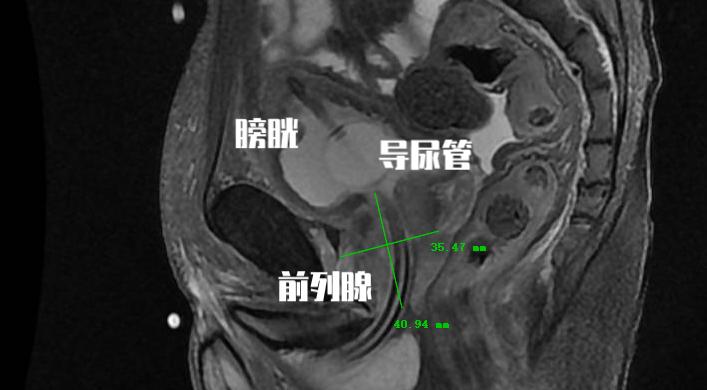

前列腺增生导致的机械性梗阻非常好理解,就是 前列腺增生时前列腺体积增大,增大的前列腺组织可挤压后尿道,前列腺部尿道伸长,变窄,排尿阻力增大。有些增生的腺体可以突入膀胱,造成膀胱出口梗阻 。经常我们和患者打比方是 “年轻的时候你的尿道如果是高速公路,那随着年龄增大,高速公路年久失修,慢慢变成了一条乡间小路” 。

这个是临床上很多患者非常关心的问题,都说非那雄胺的作用就是缩小前列腺体积, 那为什么我一直坚持在吃,但是前列腺体积每次做检查的时候仍然在增大?

总结一下,非那雄胺的适用人群是前列腺增大、下尿路症状的前列腺增生患者,前列腺体积较大(≥40ml)和/或血清PSA水平较高(PSA≥1.4ng/ml)的患者效果更好。由于非那雄胺虽然起效时间相对较慢,但是具有长期疗效稳定的特点。另外值得强调的是,虽然非那雄胺的临床作用是缩小前列腺体积,但是由于I型5α还原酶的作用,部分患者仍然会出现前列腺体积逐步增大的情况!